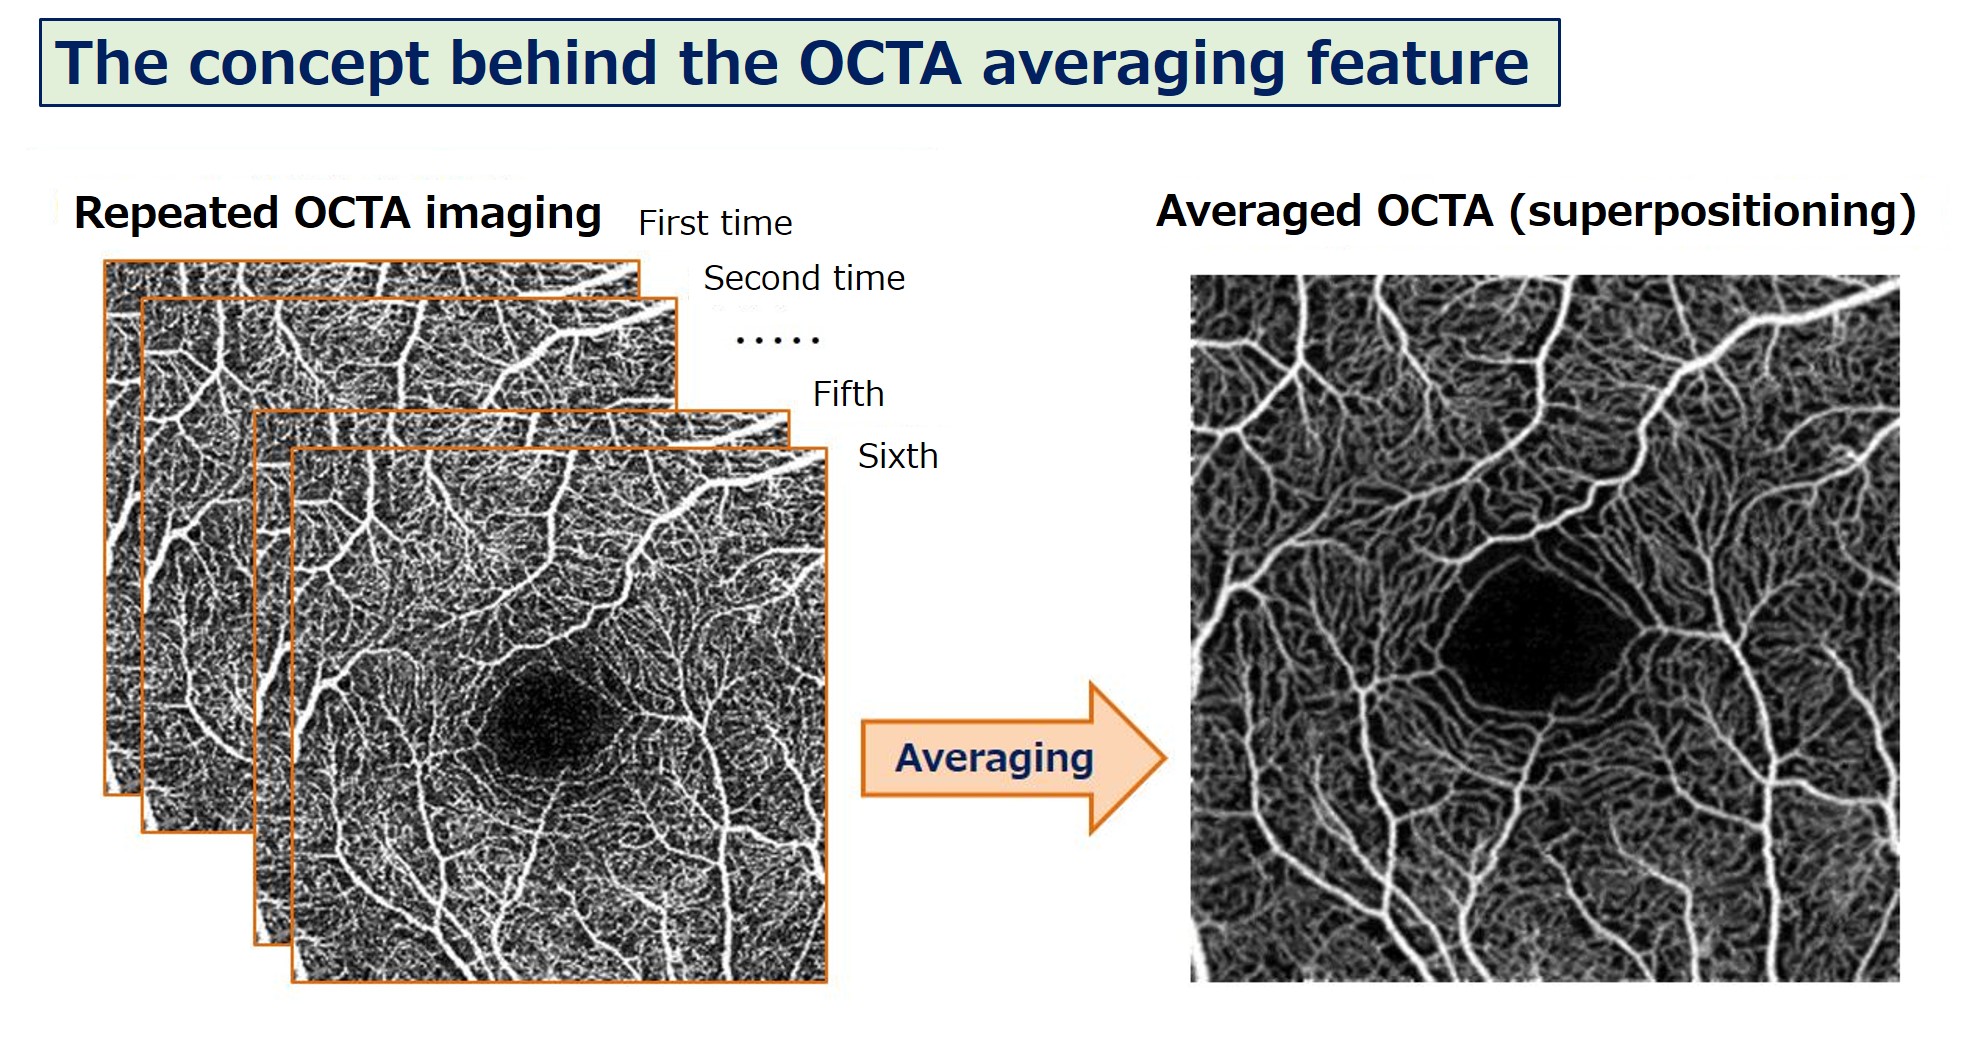

Усереднення ОКТА

“ОКТА усереднення" це метод зниження шумів зображення шляхом накладання та усереднення ОКТА зображень. Фоновий шум зменшується шляхом усереднення кількох зображень тієї самої ділянки, спотворення виправляється для отримання висококонтрастних зображень ОКТА.

Технологія усереднення ОКТА зображень (рис. 2)